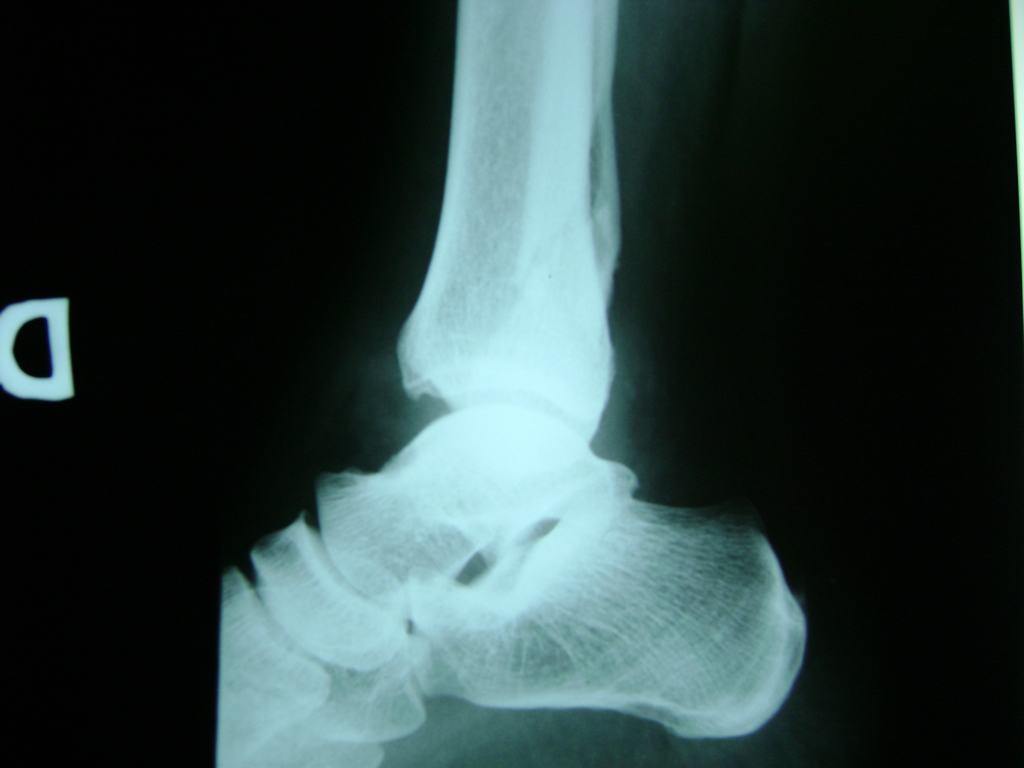

Una fractura de tobillo es la rotura de uno o más de los huesos del tobillo. Estas fracturas pueden ser:

- Los extremos de los huesos están desalineados entre sí (desplazados).

- La fractura se extiende hasta la articulación del tobillo (fractura intra-articular).

- Los tendones o ligamentos (tejidos que sujetan los músculos y los huesos entre sí) están rotos.